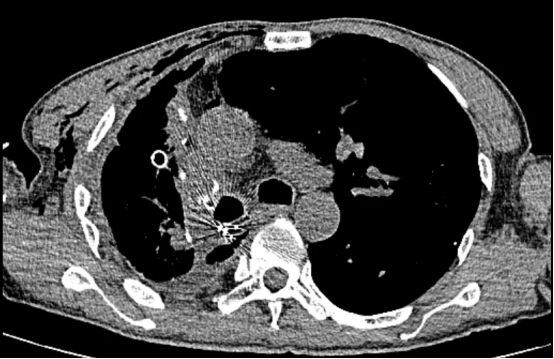

术前影像(左右滑动查看更多)

该患者为61岁男性,肺部病情错综复杂。4年前确诊肺结核后因治疗不规范,发展为“利福平耐药”结核,病情持续恶化。2年来反复咯血,虽经3次支气管动脉栓塞术暂时控制,但病灶顽固,收治入院时已形成多重诊断:毁损肺(右上)、右肺下叶鳞癌(背段)、肺曲霉菌病、陈旧性肺结核。其右肺上叶完全丧失功能,并与胸壁形成致密粘连,医学上称为“毁损肺”——胸外科领域公认的极高难度手术。